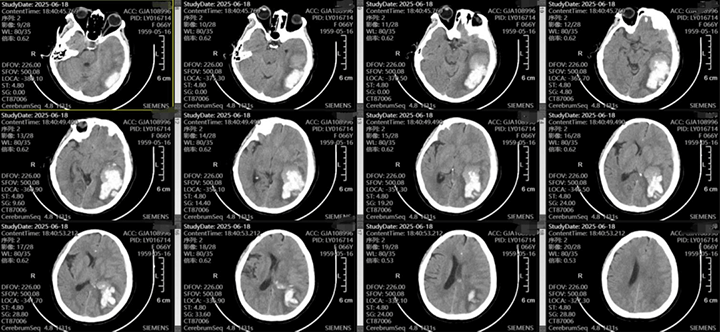

随着老龄化的加剧,脑出血的患者越来越多,不同部位的脑出血,可能因不同的原因导致,该患者左侧颞枕叶脑出血,吴全主任考虑脑血管畸形可能较高,但患者意识渐昏迷,先行血肿清除,但骨窗主要位于后枕顶部,若是去除骨瓣,不利于术后脑组织的保护,且后期需要颅骨修补,故与患者家属充分沟通后,予以骨瓣回纳,术后治疗上加强脱水,帮助患者渡过脑水肿关,患者术后第一天意识即转清楚。后期待病情平稳后在行DSA检查评估,明确此次出血是否为脑血管畸形、动脉瘤等原因导致的出血。